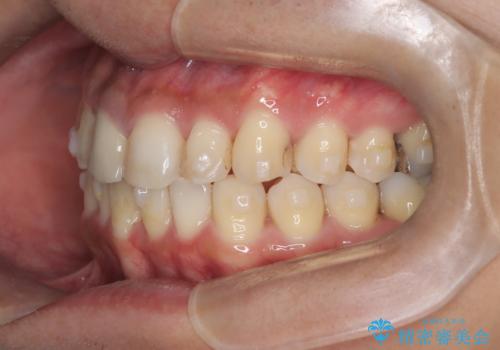

【インビザライン】八重歯と歯のでこぼこが気になる!

- 「八重歯と歯のでこぼこを治したい」を主訴に来院された患者様です。

歯は抜かずに奥歯の遠心移動とIPRで八重歯とでこぼこを改善しました。